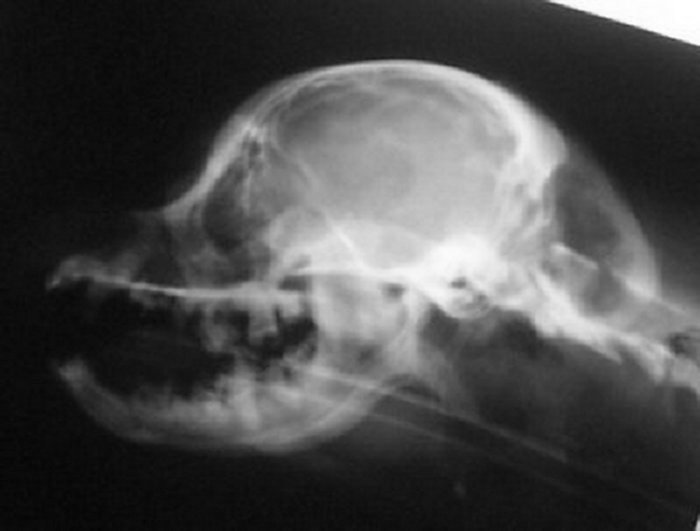

The skull x-ray of a dog with a full cerebellum is below that on

the left and the skull x-ray of a dog with a crushed cerebellum

is shown on the right. You can easily see there is a distinct

difference in the shape of the back of the skull between the two

and why the cerebellum ends up crushed. The most distinct

difference, besides the fact that the skull on the right is

shorter from front to back, is that the occiput sticks out in

the skull x-ray on the left. In the right, that occiput is still

there, but it is more downsloped and blends in with the back of

the skull to the point you can barely see it--almost like

someone took a hammer to the occiput and smashed it in.